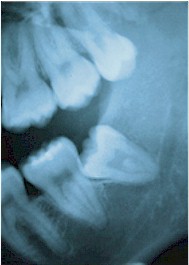

Your orthodontist can advise you about the status of your third molars.  Usually an x-ray is required for a full evaluation of your particular case.

If a third molar partly erupts, but lacks space to fully erupt, a local gum problem usually develops. Episodes of acute gum infection are common, particularly when resistance is low. The tooth should be removed.

If a third molar does not erupt, it may be left where it is.  Generally, there is little risk associated with leaving it alone and little risk associated with removing it.